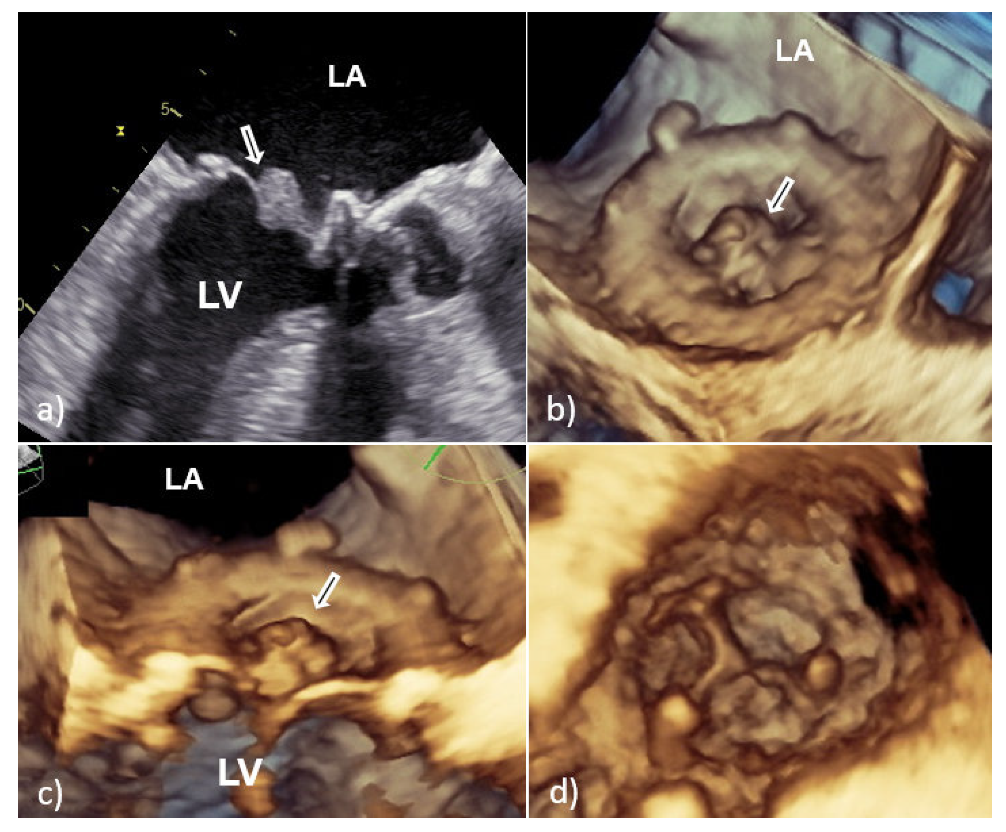

With TTE, it is more difficult to detect vegetation on PV than that involving native valves, because the highly echogenic suture ring and PV support structures can prevent detection of vegetation within the valve apparatus or its shadow [6,7]. Therefore, TEE should always be used if a diagnosis of PVE is suspected. In large series of PVE, TEE showed 86–94% sensitivity and 88–100% specificity for vegetation diagnosis; at the same time, the sensitivity of TTE was 36–69% [6,7]. Vegetative growth usually occurs as an abnormal echogenic mass with independent free movement attached to the atrial side of the mitral PV (Figure 2) [6,7].

However, vegetative growth can occur as thickening and irregularity of the normally smooth contour of the suture ring (Figure 2) or in the case of biological PVE as vegetation attached to the leaflets (Figure 3), sometimes with their consequent perforation or creation of a pseudoaneurysm [6,7].

Because the risk of embolism in patients with IE is related to the size, morphology, and mobility of vegetation, proper assessment of vegetation and monitoring of their size during antibiotic therapy have important prognostic implications [10,11]. Therefore, the accuracy and reproducibility of vegetation measurements is particularly important due to the greater effectiveness of early surgical interventions in patients with large mobile vegetation [10,11]. In this context, it is important that 2D TEE could underestimate vegetation compared to 3D TEE primarily due to limitations in selecting the maximum true diameter of irregular masses [10,11]. This shortcoming is solved by 3D TEE which allows infinite planes and volumetric reconstruction of masses (Figure 2). Because the main diameter of vegetation is important in the assessment of medical treatment response, as well as for setting a surgical indication in patients without other surgical indications, differences between the two TEE techniques in accuracy of vegetation measurements may have key therapeutic implications. In addition, 3D TEE allows better morphological classification of vegetation (e.g., filiform, sedentary, and clustered), and recognition of those associated with fragility and embolization (it seems that sedentary vegetation has the least embolic potential) [10,11]. Therefore, the main advancement of 3D TEE over 2D TEE is better assessment of vegetation characteristics—size, location, number, morphology, consistency, mobility, and relationship to valve structure—resulting in better prediction of potential embolic risk [10,11].

Figure 2. Transesophageal echocardiography of mechanical MVP endocarditis caused with Staphylococcus aureus: 2D TEE showed an extensive vegetation (white arrows) attached to the prosthetic ring and leaflets (a,b); 3D TEE showed voluminous vegetation (asterisks) affecting a whole circumference of sewing ring and MVP leaflets (c—in systole, d—in diastole). 2D TEE—two-dimensional transesophageal echocardiography; 3D TEE—three-dimensional transesophageal echocardiography; LA—left atrium; PVE—prosthetic valve endocarditis; and MVP—mitral valve prosthesis.